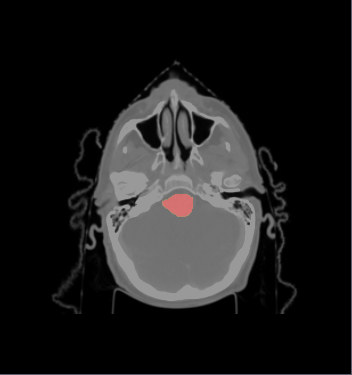

- We selected the ROI of every data excluding lung and chest. For each data there exist the segmentations of brain stem, left and right parotids. For example

- We constructed the average atlas of 20 datasets of ROI, and merged the segmentations into the average atlas. These segmentations are the probability maps of

brain stem, left and right parotids.